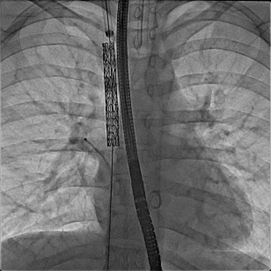

Figure 6

Fluoroscopic still image: AP view, covered stent in SVC excluding anomalous right pulmonary vein and extending to ASD part of the defect. The balloon is inflated to flare up the distal part of the stent to close the ASD. Note a catheter is kept in the anomalous pulmonary vein to continuously measure pressure and check for obstruction during and/or after the balloon is fully inflated.

AP: anteroposterior, ASD: atrial septal defect